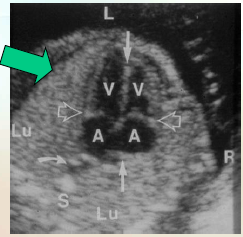

what does the T sign mean?

why does it look that way?

it rules out 90% of pathology

both valves are closed

what part of the heart is always closest to the AO?

rt atrium

how can you tell the baby position?

what can you say abou the lungs?

what can they indicate?

by the diaphragm (A, P, S, I) long to baby

Echotexture is homogeneous with medium level echoes

Early in gestation lung echogenicity is less than or equal to liver

Later in gestation lung echogenicity is greater than liver

Lung echogenicity can be an indicator for lung maturity & can be verified by amniocentesis with L/S (Lecithin-Sphingomyelin) ratio. In this image b/c the lung echogenicity is > liver you can tell it’s further along ~ 30wks

where is the apex?

on the anterior surface pointing slightly to the rt

there is rib shadow on th elt